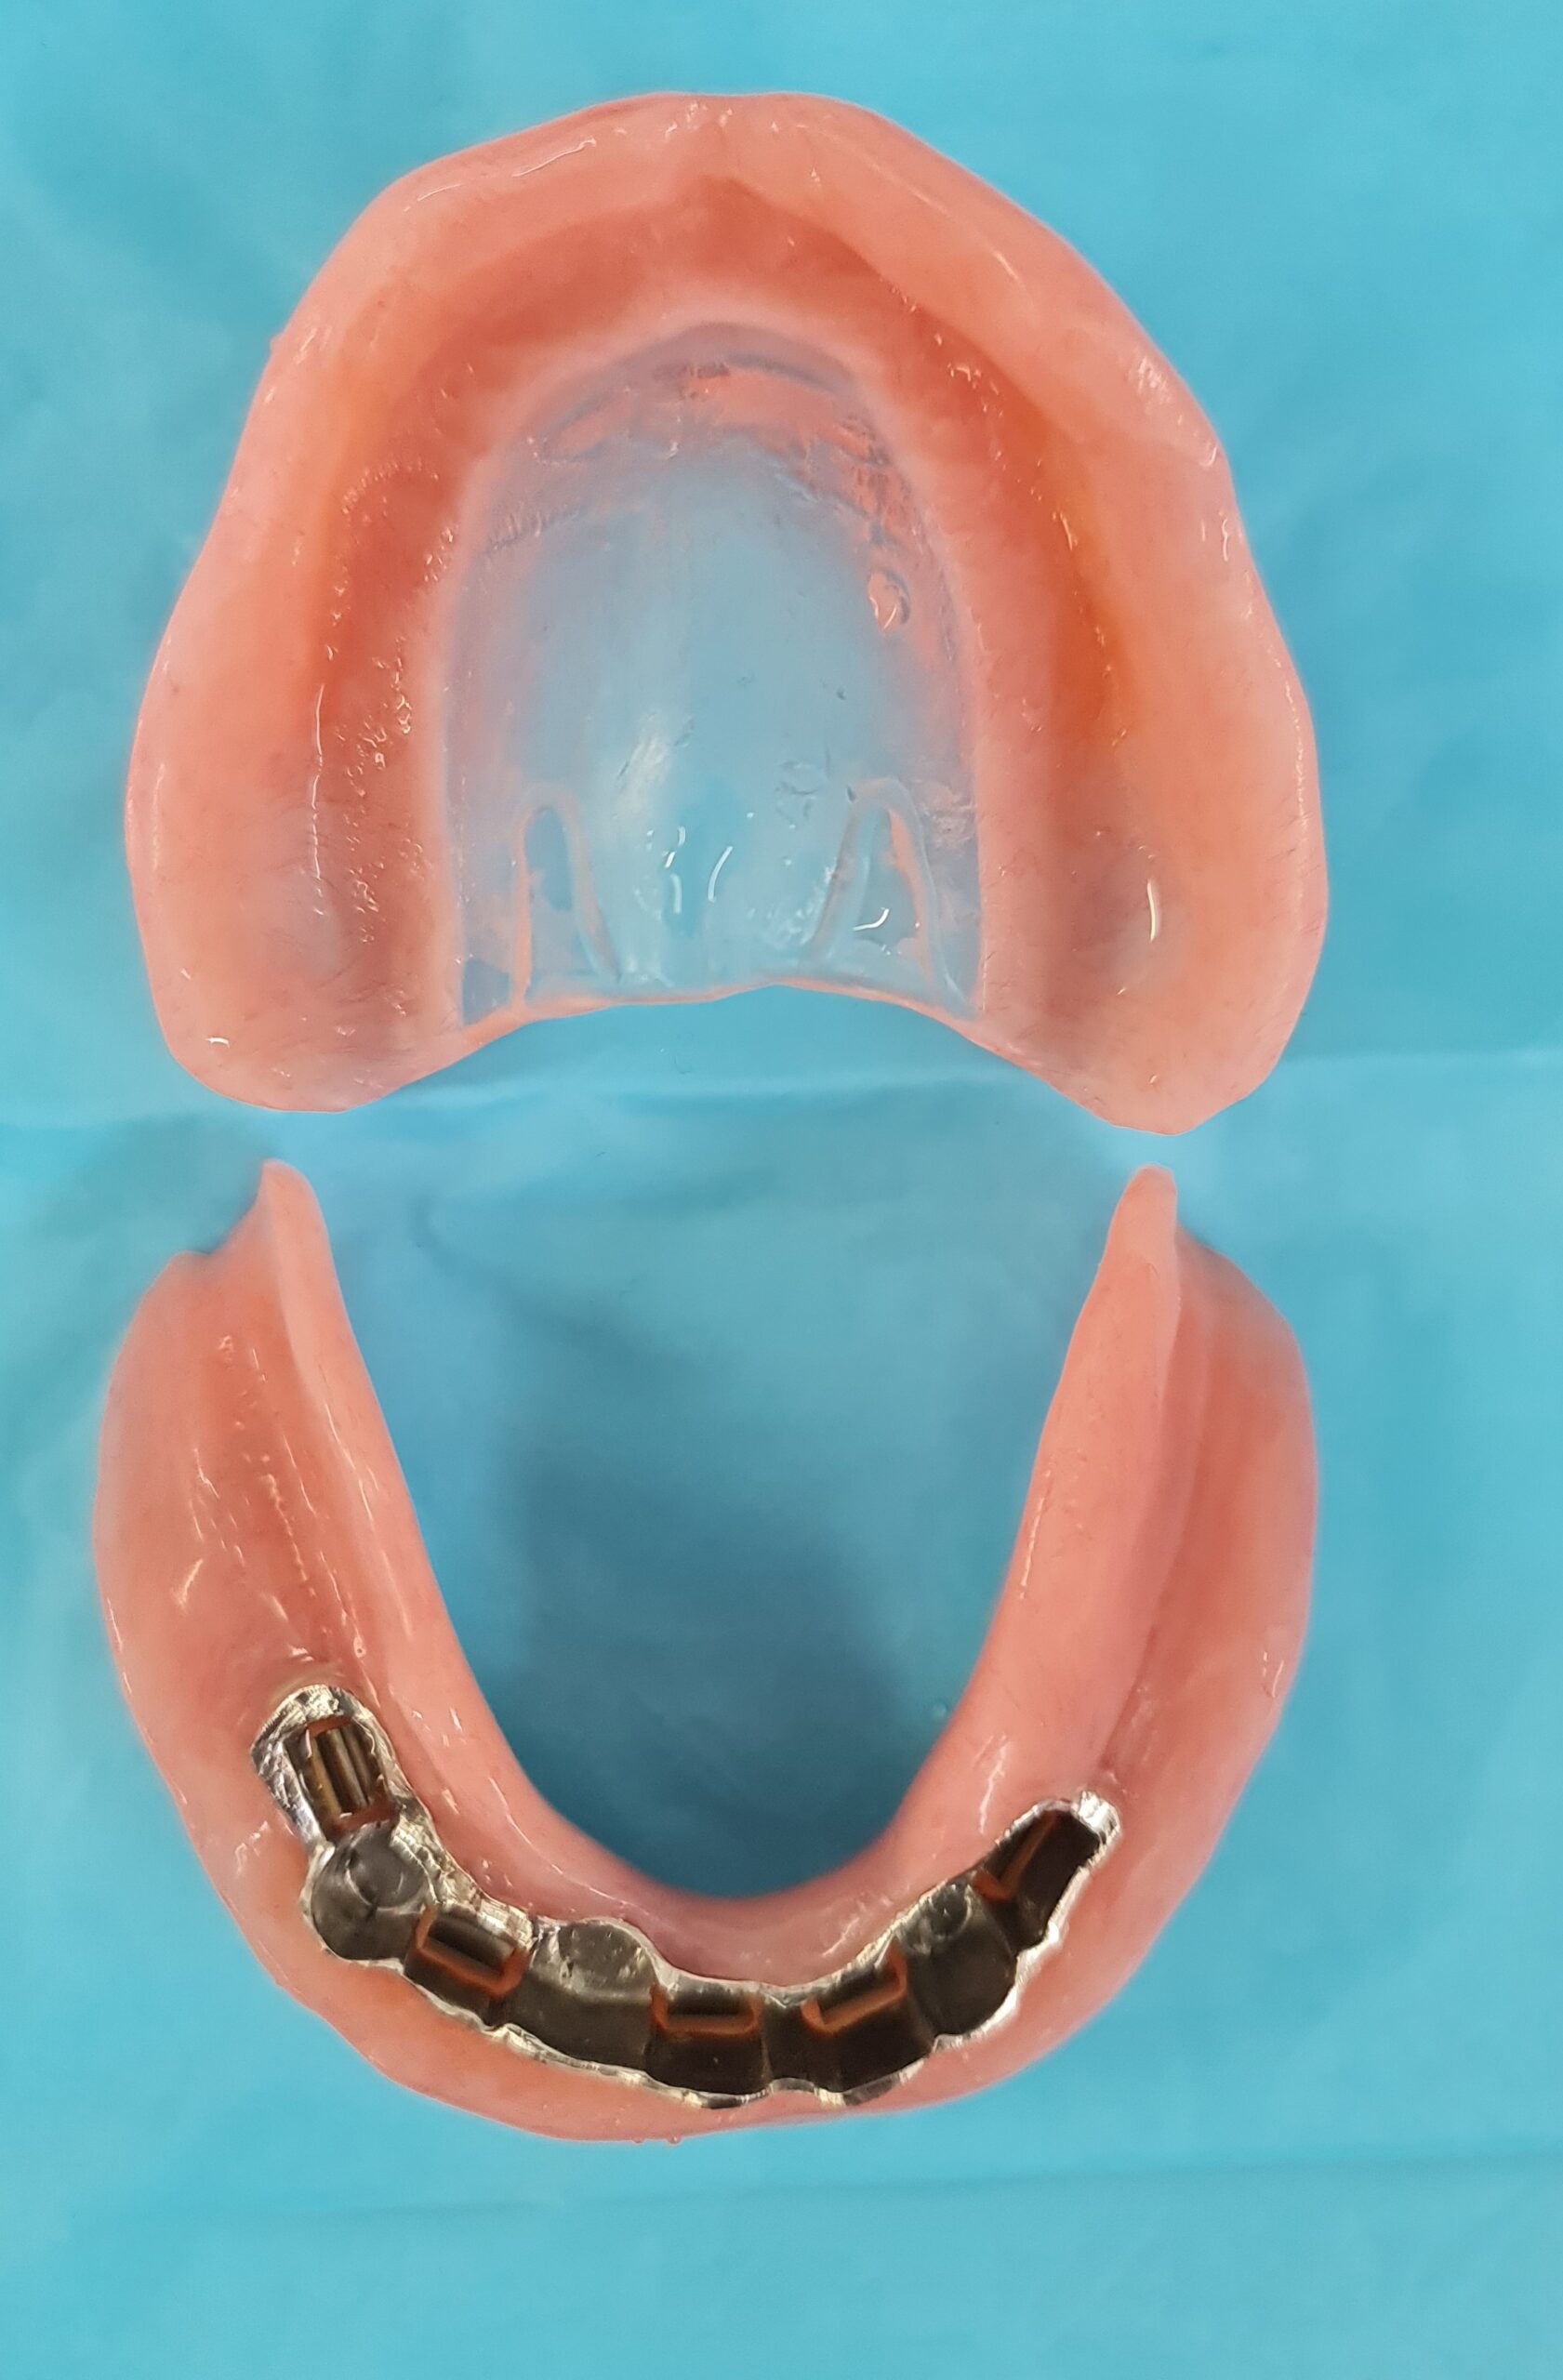

There are two types of implant dentures: bar-retained and ball-retained. In both cases, the denture will be made of an acrylic base that will look like gums. Porcelain or acrylic teeth that look like natural teeth are attached to the base. Both types of dentures need at least two implants for support.

- Bar-retained dentures — A thin metal bar that follows the curve of your jaw is attached to the implants that have been placed in your jawbone. Clips or other types of attachments are fitted to the bar, the denture or both. The denture fits over the bar and is securely clipped into place by the attachment

Lower Jaw Bar Implant Overdentures